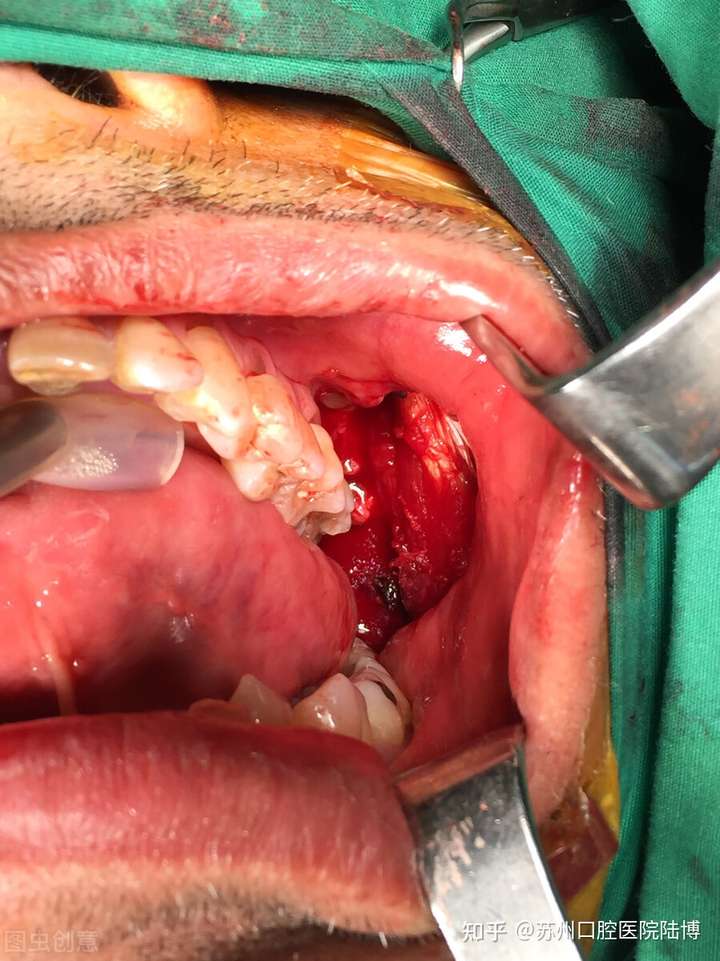

口腔癌

口腔癌是发生在口腔的恶性肿瘤之总称,

占全身肿瘤的5%—6%,

是世界上6种最常见的癌症之一。

根据临床统计,在口腔癌的患者中,90%为吸烟者,

其中男性吸烟者的患癌率是不吸烟者的4倍,女性则为9倍之多。

大量的流行病学研究已经证实吸烟与口腔癌密切相关,

吸烟人群中口腔癌的发生率及死亡率比不吸烟者要高2-3倍。

此外,吸烟可以加重再次发生口腔癌的危险性。口腔癌治愈后继续吸烟者40%可发生第二原发癌,而治愈后戒烟者仅6%,非吸烟者治疗后的5年生存率明显高于吸烟患者。